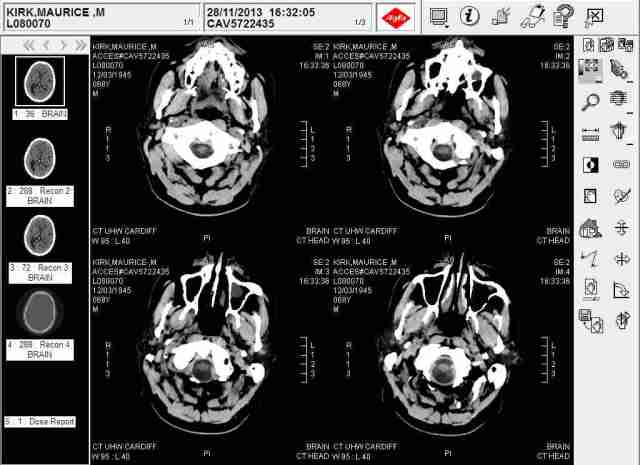

- The enclosed brain scans had been disclosed to me in custody simply to try and fool me while sixteen, no less, Caswell Clinic other professionals opposed XX and Professor Rodger Wood of Swansea University deliberate falsification of the fact. This was proved in France following my acquittal from your ‘machine-gun’ malicious prosecution.

HMP Swansea Brian Scan

EVIDENCE OF A JUDGE RICHARD THOMLOW CONSPIRACY DESCRIBED BRAIN TUMOUR

- 2nd December 2009 Cardiff Crown Court hearing when XX was present before HHJ Neil Bidder QC to support, the now judge Richard Twomlow’s police application for a permanency , having run out of their mandatory maximum incarceration time of their victim, under section 35 of1983 Mental Health Act, in Caswell Clinic. I was to be transferred to Ashworth High security psychiatric hospital, indefinitely, due to permanent brain damage from a brain tumour despite the ‘patient’ yet to be informed of its existence!